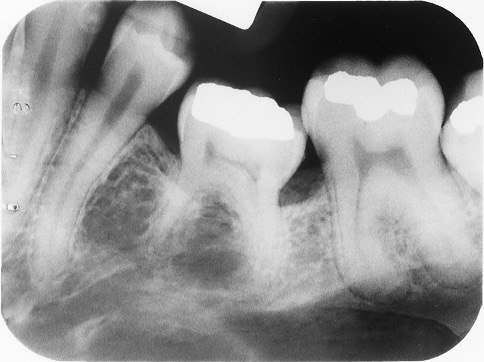

5. What is the condition in the distal surface of the tooth # 3.3?

6. What is the condition on dista surface of the tooth # 3.7?

7. What condition can be seen in the tooth # 4.4?

8. What condition can be seen in the distal surface of the tooth # 2.4?

9. What condition can be seen in distal surface of the tooth # 2.6?

10. What condition can be seen on the teeth # 1.5 and 1.4?